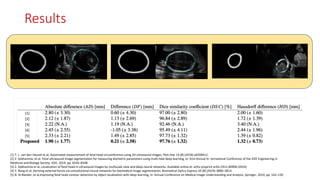

Results

[1] [2] [3] [4] [5] [1] T. L.van den Heuvel et al, Automated measurement of fetal head circumference using 2D ultrasound images, PloS One 13 (8) (2018) e0200412. [2] Z. Sobhaninia, et al. Fetal ultrasound image segmentation for measuring biometric parameters using multi-task deep learning, in: 41st Annual In- ternational Conference of the IEEE Engineering in Medicine and Biology Society, IEEE, 2019, pp. 6545–6548 [3] Z. Sobhaninia et al, Localization of fetal head in ultrasound images by multiscale view and deep neural networks, Available online at: arXiv preprint arXiv:1911.00908 (2019) [4] Y. Rong et al, Deriving external forces via convolutional neural networks for biomedical image segmentation, Biomedical Optics Express 10 (8) (2019) 3800–3814. [5] B. Al-Bander, et al,Improving fetal head contour detection by object localisation with deep learning, in: Annual Conference on Medical Image Understanding and Analysis, Springer, 2019, pp. 142–150 Results